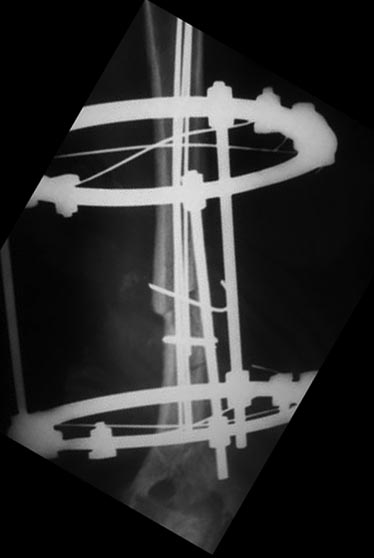

Уважаемые коллеги, прошу прощения за задержку ответа. Операцию проводили 27.11.13г по настоятельной просьбе докторов там, где был оперирован, поэтому пришлось долго ждать контроль.Р-грамму и самого больного, только сегодня приехали. Операция более 4 часов, во время операции установлено полное повреждение лучевого нерва, концы булавовидно утолщены, дефект 2,5-см, с трудом и очень долго пришлось мобилизовать, частично был замурован костной мозолью . Кость укорочена на 3 см, пластика типа русского замка, в это время часть дистального отломка откололась, поэтому пришлось фиксировать винтом, и еще косо спицей., и/м 4-мя спицами, шов нерва, под нервом слой мышца, АВФ из двух колец с компрессией. Р-снимки прилагаются.

P.S. Со слов больного на днях начались периодические стреляющие боли в дистальной части руки.